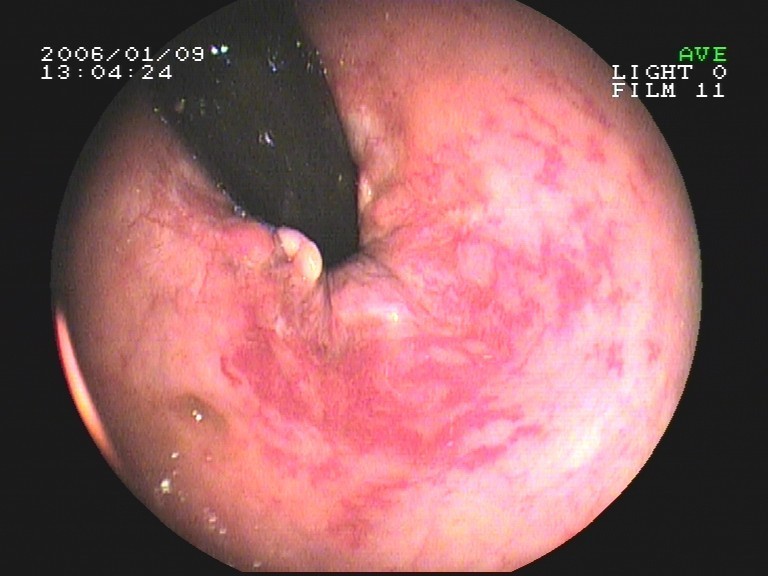

Coloskopie - chronische Strahlenproctitis (Entzündung der Mastdarmschleimhaut nach Strahlentherapie)